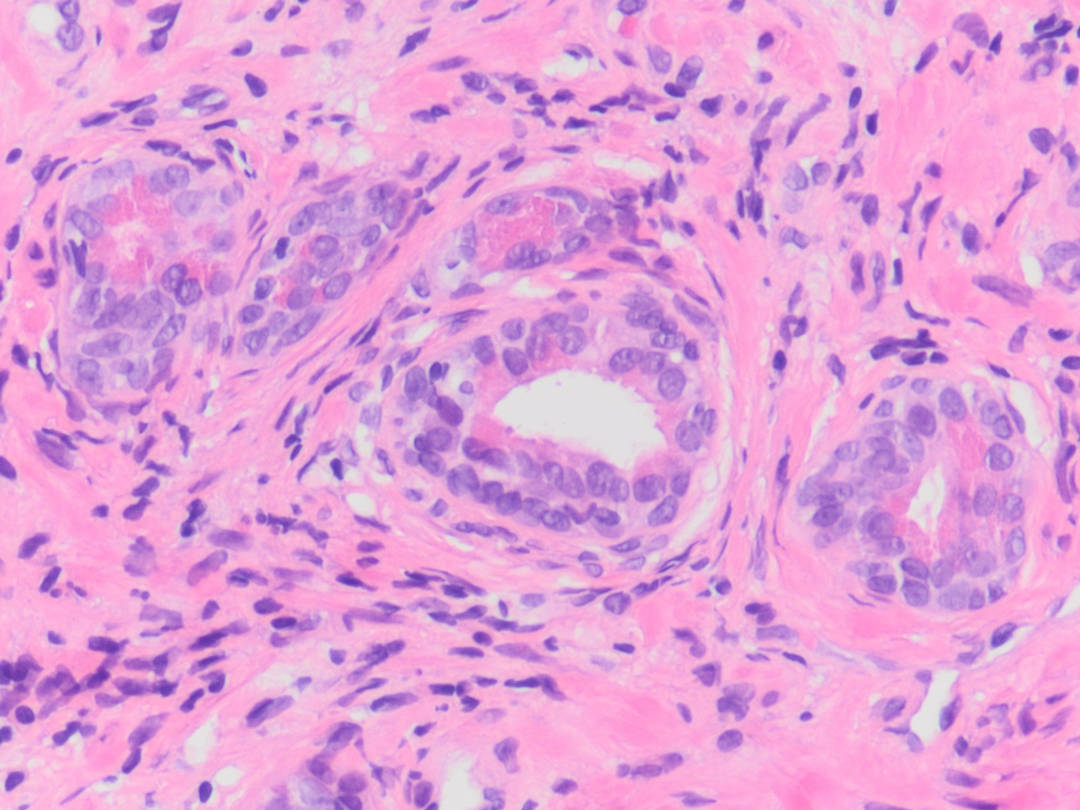

PATOLOGÍA QUIRÚRGICA.

En patología quirúrgica proporcionamos servicios de diagnósticos para todos los especímenes de tejidos (biopsias y resecciones) de cualquier origen. Nuestra experiencia en una amplia gama de patologías neoplásicas y no neoplásicas, nos permite entregar información completa de diagnóstico, pronóstico y predictivo a nuestros colegas médicos y sus pacientes.